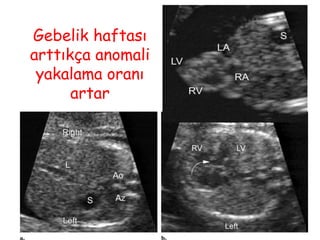

Gebelik haftası

arttıkça anomali

yakalama oranı

artar